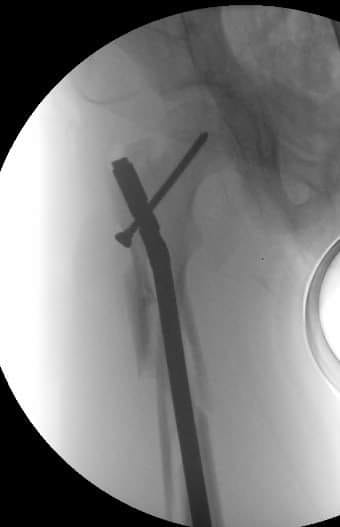

Вот, что получилось.

Александр, Почему в шейку и головку? почему не в направлении малого вертела привели блокирующий винт? Это оригинальный винт или...?

почему бы и не в шейку... Если есть такая дырочка и в гвозде, и в направителе. В physis винт не проникает.

Винт, конечно, из набора.

Винт, который проходит перпендикулярно зоне роста проблем не вызывает. Таким образом делается эпифизиодез при юношеских эпифизиолизах и в перспективе на рост кости не влияет. Поэтому производитель не зря придумал шеечный винт в данном стержне

Эпифизиодеза у нас в планах не было, поэтому винтик не до суставной поверхности. В общем, если железка не проходит через зону роста, то и беспокоиться особо не о чем, правильно?

На прямой проэкции видно, что винт проходит физиодезный мостик. Даже если был бы длиннее, тоже не критично.

Супер, гвоздь с латеральный точкой доступа! Кто производитель?

В чем смысл настолько латерального захода, почему так спереди гвоздь и настолько кзади винт?

смысл латерального захода - отдалиться от сосудов, питающих у детей головку бедра. Если сделать снимок с чуть большей внутренней ротацией, не будет складываться впечатления, что он спереди. Винтик... Он внутри шейки, не торчит. Этого, полагаю, достаточно. Был бы он кпереди на несколько мм, это бы ничего не прибавило